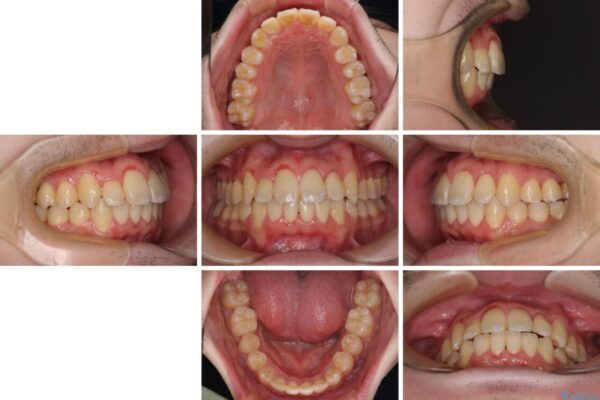

八重歯や奥歯の噛みにくさを気にして来院された患者様です。

前歯のクロスバイトや八重歯の他に、左右最後臼歯のシザーズバイト(鋏状咬合)が認められました。

シザーズバイト改善のために補助装置を使用しながら、ワイヤー装置にて全体の歯列を整えることとしました。

治療後

• 全顎的なクロスバイト 補助装置を用いてワイヤー矯正 治療後画像